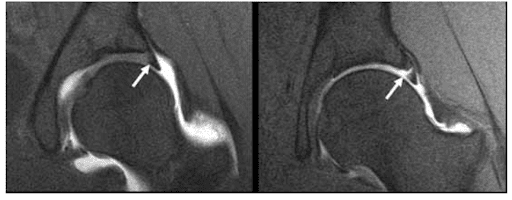

Do I Need an MRI with Contrast for a Hip Labral Tear?

Written by Tanner Besse, OMS IV LECOM, reviewed by Dr. Torrance If your doctor orders an MRI for hip pain, you might be told you need “contrast dye” injected into